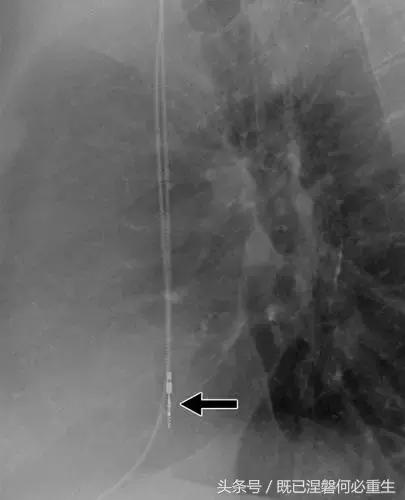

图。 7A 79岁的男性患有电极折断和迁移。

A,初始胸前X线片显示Pacesetter双腔起搏器低于锁骨的心房导线不完全断裂(变薄)(箭头)。

图。 7B 79岁的男性患有电极折断和迁移。

B,大约3年后,电极完全断裂,金属传导碎片(箭头)分离。 远端片段(箭头)已经偏移尾侧,但是由于围绕电极的射线可穿透鞘的束缚效应而没有迁移到肺循环中。 引线和中心静脉导管最常见于锁骨和第一肋骨之间断裂,因为它们在臂运动期间被锁骨下肌肉或腱或肋锁韧带压缩[16]。